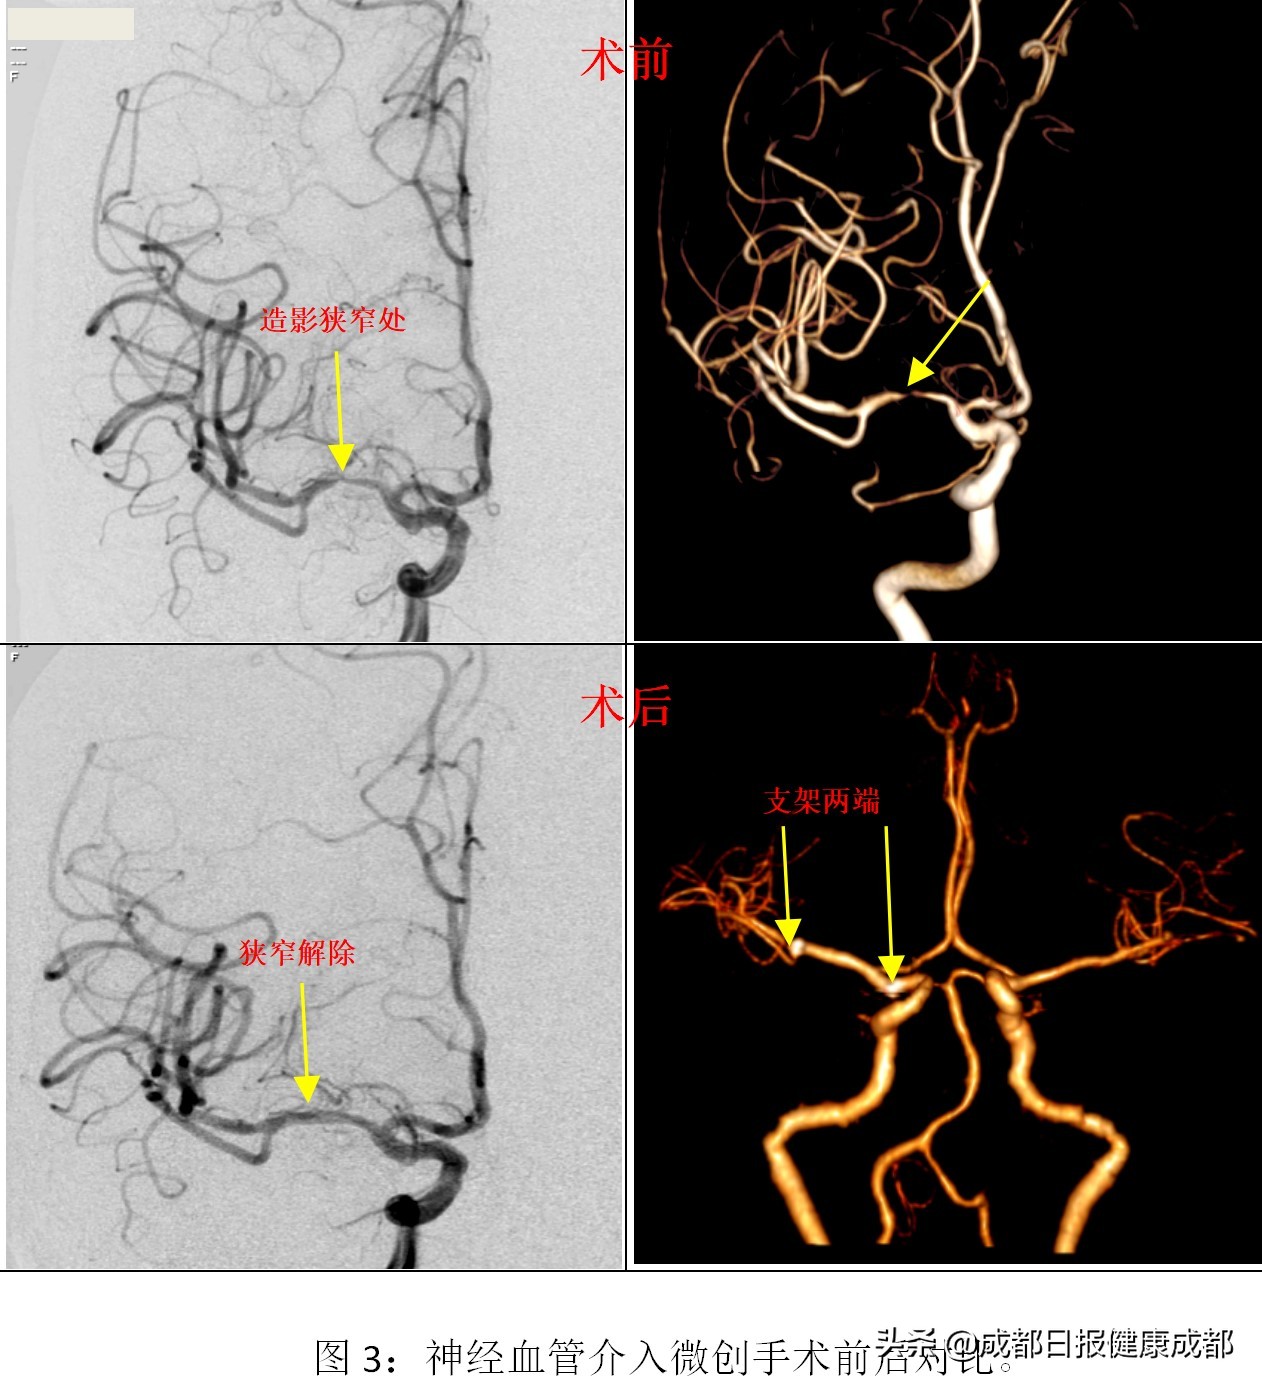

这是一种怎样的微创手术?医生需要在大腿根部开一根针眼大小(1mm左右)的切口,在血管内插一根管子,利用一根细如头发丝的导丝通向大脑,然后把球囊放置于狭窄处进行扩张,将狭窄解除后放置一个金属支架对血管进行再成型治疗。

之所以称之为微创手术,因为本是颅内脑血管的手术,手术切口却在大腿根上,而且只有针眼大小;其次,也是本次手术最关键的技术在于“头发丝”细的微导丝的精准指引,引导所有手术器械在血管内穿行,并能准确到达细小到1-2毫米的脑血管病变处,最终完成手术。

7月3日,李阿姨进行了微创神经血管介入手术治疗。1.5小时后手术顺利完成,血管狭窄完全解除。李阿姨麻醉复苏后感叹道:“这么快?脑袋里的手术做完了?”

专家说,对于症状性颅内动脉粥样硬化性狭窄,强化药物治疗不能有效的预防卒中复发,其年卒中复发率仍高达 20%。既然如此,就要采取其他治疗方法。目前,世界上主要的治疗方式就是血管内治疗(微创),包括球囊血管成形术、支架置入术(如下图)。

最新研究显示,血管内治疗技术成功率在95%以上,支架治疗不良事件发生率仅为2.6%,再狭窄率为3%。所以,已经是比较安全的一种治疗方式。